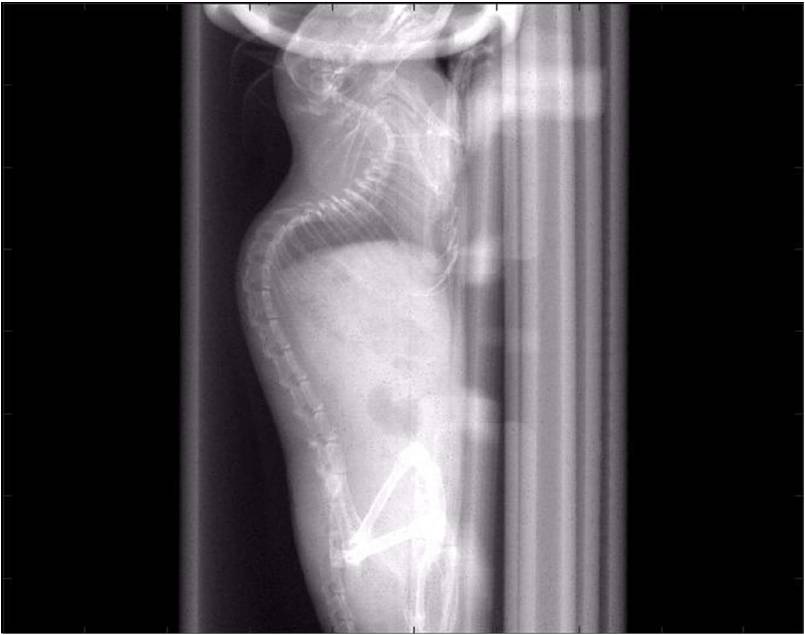

ChiPet 100是一款針對離體骨,小鼠,大鼠及兔子等動(dòng)物進(jìn)行多功能3D掃描的Micro-CT系統。

可以測量骨參數、棕色脂肪、皮下脂肪、脂肪肝、血管、腫瘤轉移等參數。

檢測案例

肺轉移

小鼠模式,22.5μm像素

正常

8天 14天

無(wú)造影劑注入 造影劑注入